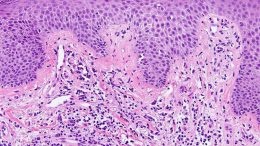

It is said that “the skin is the window into the body” and therefore we can see various manifestations of the skin in health and in many diseases. For example, try examining “dermographism” with yourself or your child. Make a line or cross on your upper chest by pressing your finger. In a moment in people with increased irritation, a distinctive pattern appears, rising above the surface, as is known in urticaria.